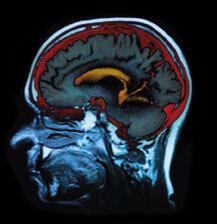

Le cerveau a besoin de DHA

Le DHA est l'un des principaux acides gras polyinsaturés du cerveau. Il apporte la fluidité membranaire nécessaire aux cellules nerveuses pour que les impulsions nerveuses électriques puissent circuler facilement dans les circuits cérébraux.

Lorsque les niveaux de DHA sont faibles, la production de prostaglandines, d'importants régulateurs de l'impulsion nerveuse, est déstabilisée. Ensuite, une inflammation des prostaglandines se produit dans le cerveau semblable à celle que l'on trouve à l'origine de problèmes articulaires ou digestifs.

Plus récemment, de faibles niveaux de DHA ont été reliés à de faibles niveaux de sérotonine dans le cerveau qui, encore une fois, est connecté à une augmentation de la tendance dépressive, suicidaire ou à la violence. Une consommation élevée de poisson a également été associée à une diminution significative des pertes de mémoire et des troubles cognitifs liés à l'âge ainsi qu'à un plus faible risque de développer la maladie d'Alzheimer. Une étude a montré que lorsque l'on donne une supplémentation en huile de poisson à des patients atteints de maladie d'Alzheimer, leur qualité de vie s'améliore de façon significative.

Produits de la mer et développement de l'enfant. Le cerveau est riche en acides gras polyinsaturés de la série des Oméga3. Le plus important d'entre eux, le DHA est nécessaire au développement harmonieux des fonctions cérébrales, en particulier, pour celui de la vision, qu'une carence peut perturber de façon durable.